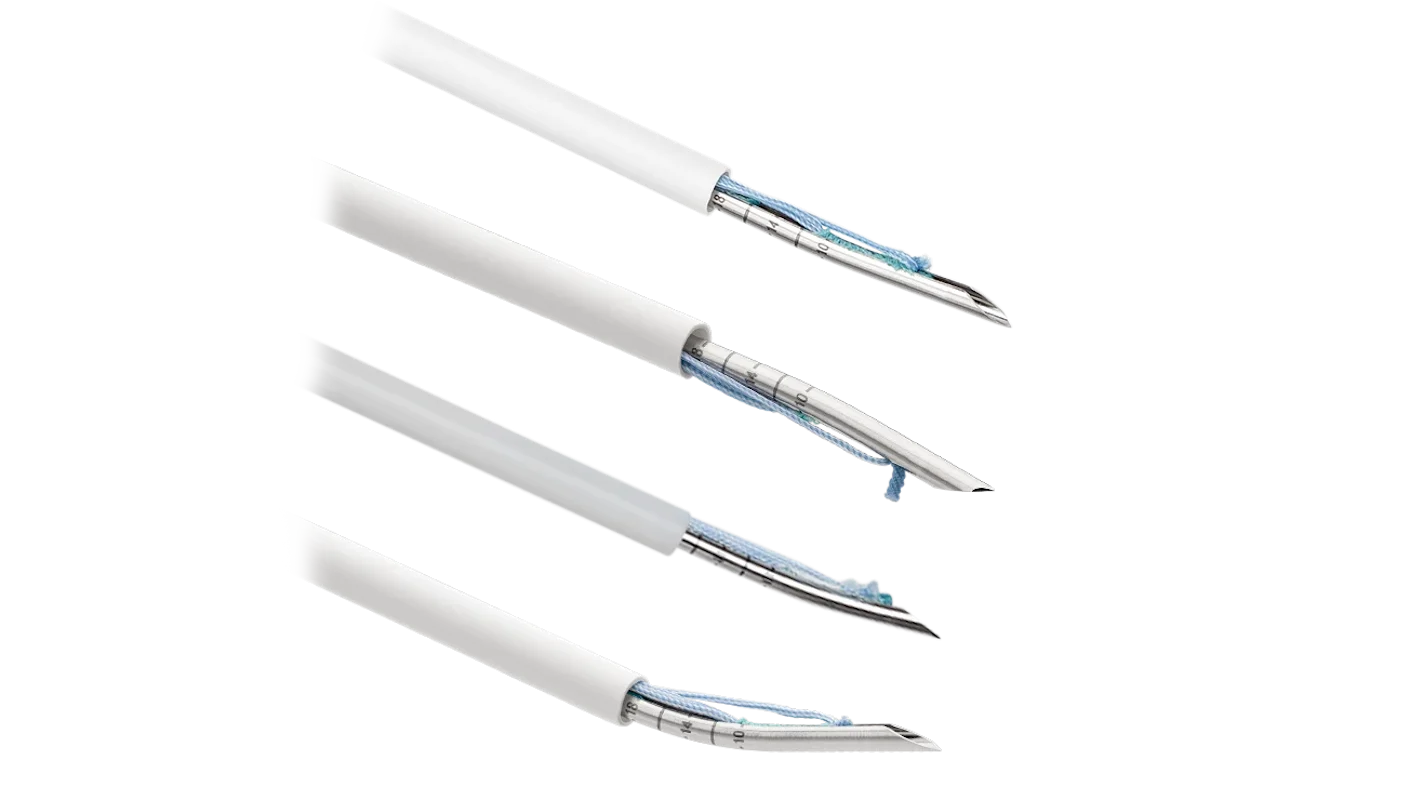

Arthrex es líder global en soluciones para artroscopía y medicina deportiva, ofreciendo implantes, suturas e instrumentación desarrollados para lograr reparaciones más fuertes, reconstrucciones anatómicas y una recuperación más rápida del paciente. Nuestro portafolio cubre hombro, rodilla, tobillo y muñeca, con tecnología de última generación para cada procedimiento.

- Consumibles

- Instrumental